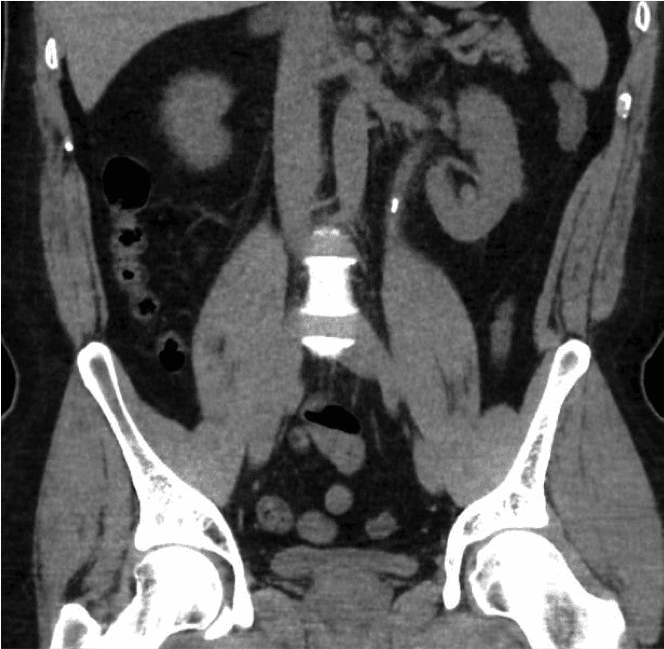

ஆரம்பத்தில் சிறுநீரில் இரத்தம் இருக்கிறதா என்று சோதிக்கவும், சிறுநீர் தொற்று இல்லை என்பதை நிரூபிக்கவும் சிறுநீர் டிப்ஸ்டிக் சோதனை செய்யப்படும். சிறுநீரக செயல்பாடு மற்றும் கால்சியத்திற்கான இரத்த பரிசோதனைகள் செய்யப்படுகின்றன. கல்லைக் கண்டறியும் உறுதியான சோதனை வயிற்றின் ஒரு சாதாரண CT ஸ்கேன் (CT சிறுநீரக சிறுநீர்ப்பை பகுதி அல்லது CT KUB) ஆகும். இது கற்களின் அளவு மற்றும் நிலையைக் காண்பிக்கும், இது சிகிச்சையைத் திட்டமிட உதவும்.